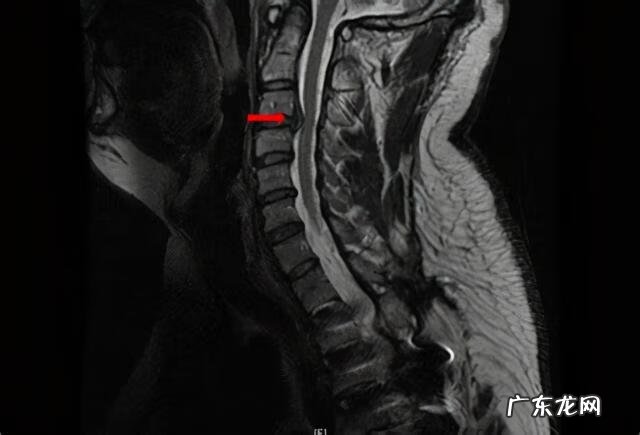

确诊的方式包括放射线检查和CT检查或者核磁共振检查,都可以看到局部神经受压的表现 。